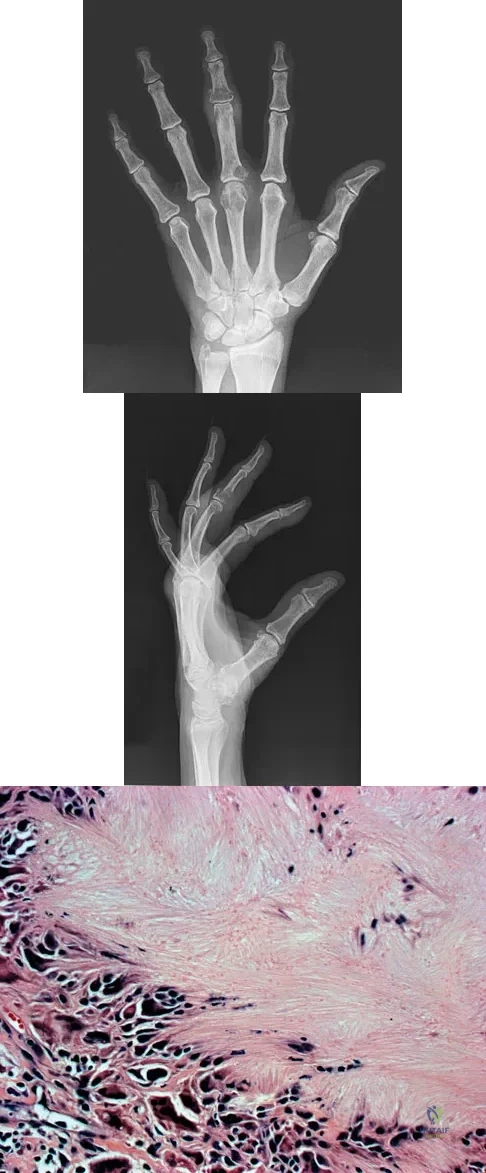

An 83-year-old woman reports pain in her left middle finger after a minor injury. Laboratory studies show a WBC count of 7,000/mm3, an erythrocyte sedimentation rate of 3 mm/h, a uric acid of 10.4 mg/dL, and a normal serum protein electrophoresis. Radiographs are shown in Figures 49a and 49b. A core biopsy specimen is shown is Figure 49c. In addition to treatment of the finger fracture, treatment should include